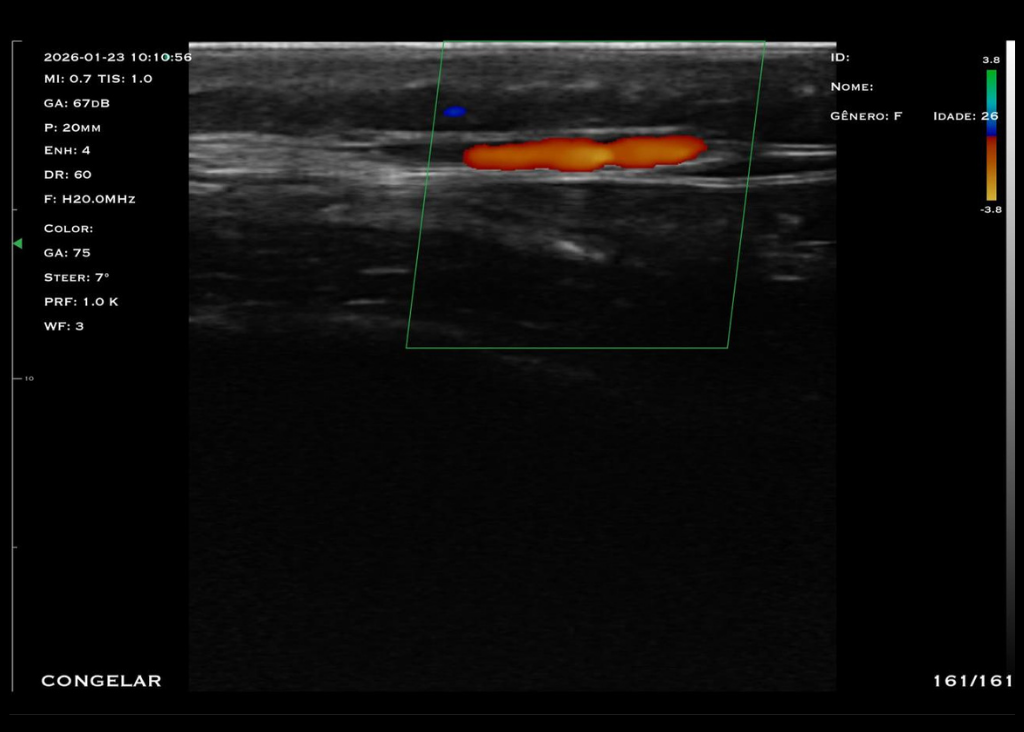

Com tecnologia linear de alta frequência (10 a 14 MHz), o modelo M4D é a escolha ideal para quem busca alta resolução em exames superficiais, com foco em detalhamento e precisão.

O trasdutor linear oferece imagens nítidas e detalhadas, permitindo a visualização precisa de estruturas como pele, tecido subcutâneo, músculos, tendões e articulações. A alta frequência garante excelente resolução para exames que exigem detalhamento extremo.

Frequência: Linear (16 – 20 MHz)

Profundidade: Até 4 cm

Modos: B, B/M, Color, PDI e PW

Aplicações: Visualização de articulações periféricas, avaliação de estruturas faciais, preenchedores, acesso PICC, acessos superficiais, anestesia pediátrica e bloqueios periféricos.